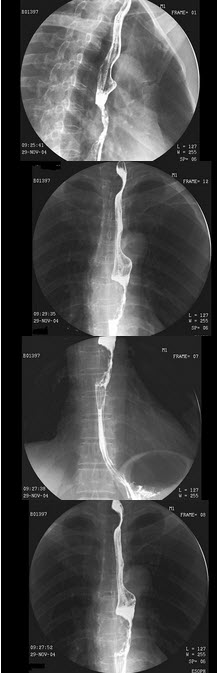

104、单项选择题

男,70岁,进行性吞咽困难半年,结合图像,最可能的诊断为()